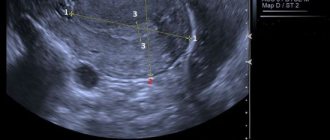

- ультразвуковое исследование органов малого таза и нижних конечностей, позволяющее осмотреть матку, яичники и мочевой пузырь и увидеть, имеется ли варикоз органов малого таза.

- допплерографическое исследование, чтобы выявить особенности кровообращения в сосудистых образованиях, которые локализовались в данной области